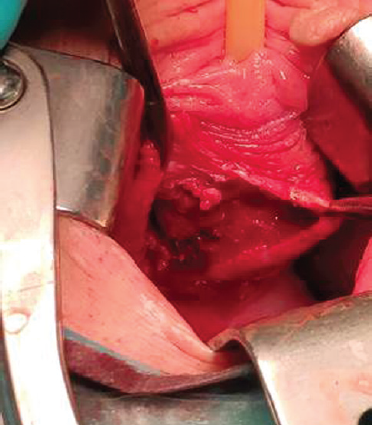

Surgery course. An incision was made along the anterior wall of the vagina after hydropreparation (Fig. 2). A paraurethral cyst with a diameter of about 6 cm was bluntly and sharply separated (Fig. 3). Its walls were excised (Fig. 4). The bladder was filled up to 250 cm; there was no urine leakage into the wound. The cyst bed (Fig. 5) was sutured with interrupted sutures (Vicryl 3–0). A Bülau drain was installed in the wound to the cyst bed, the incision of the vagina was sutured, and hemostasis was performed. A tampon was placed in the vagina. The urinary bladder was drained with a Foley catheter 18 Ch.

Fig. 2.Incision along the front wall of the vagina in the projection of a paraurethral cyst

Рис. 2.Разрез по передней стенке влагалища в проекции парауретральной кисты

Fig. 3.Exposure of the paraurethral cyst walls

Рис. 3.Выделение стенок парауретральной кисты

Fig. 4.Exposure of the paraurethral cyst walls

Рис. 4.Иссечение стенок парауретральной кисты

Fig. 5.Paraurethral cyst’ bed

Рис. 5.Ложе парауретральной кисты